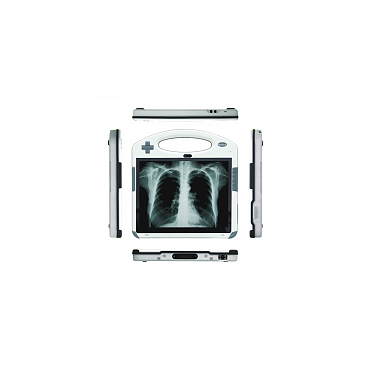

Alpha Tech Medical Services medical grade computers are ideal for operating practitioner's office, nursing stations, and in pharmaceutical processing.

The medical PCs are designed with patient safety and hygiene in mind and are certified so that you can be sure that your computer meets or exceeds the highest medical standards.